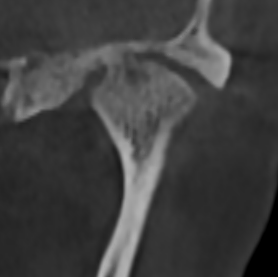

У здорового височно-нижнечелюстного сустава суставные поверхности гладкие и ровные. Такие суставы, как правило, восстанавливаются быстро.

Но, ко мне приходят пациенты с изменёнными суставными поверхностями в виде артроза. Эти суставы повреждены, и в них нарушено нормальное вращение.